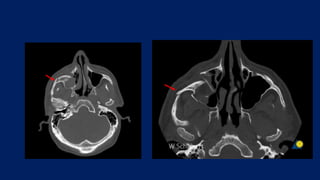

• CT- Facial bones – gold standard

• 3D CT – normal vs abnormal rim and malar eminence

DIAGNOSIS • History • Clinicalexamination • X-ray Water’s view - Zygoma buttresses, orbital floor, inf. orbital rim, ZF suture, ZM buttress Caldwell view – ZF suture • CT- Facial bones – gold standard • 3D CT – normal vs abnormal rim and malar eminence